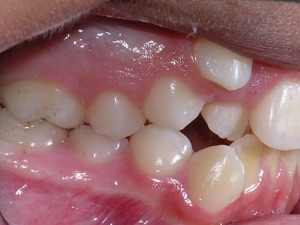

Here’s an example from a young boy who had very significant crowding. One can see that the canines on top and bottom are blocked out. There was also an overbite. The combination made the case challenging. Watch.

First Premolars were removed. We used an anchor device on the top jaw known as a “Nance” holding arch to help us retract the canines into the first premolar space. The holding device is used to reduce shifting of the top back teeth forward.